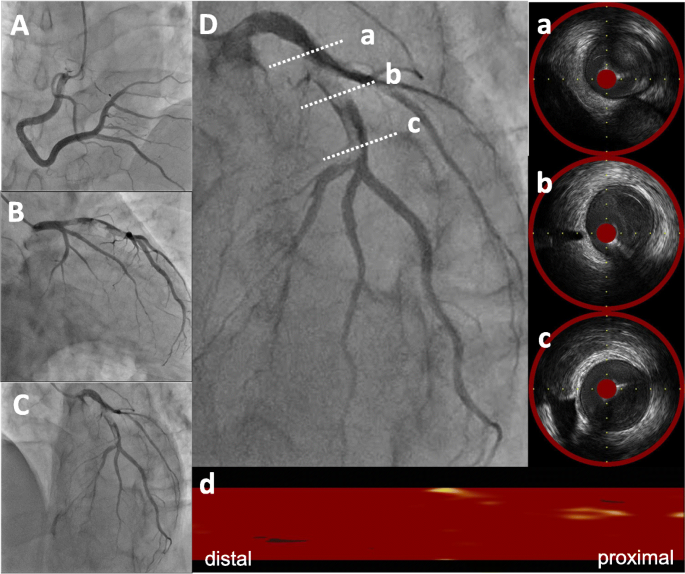

A 49-year-old Japanese man had splenic infarction with unknown cause 2 years ago. He had continued to take warfarin as anticoagulant therapy, but stopped taking the medication as self-judgment several months ago. He had no classical arteriosclerosis factors (hypertension, dyslipidemia, diabetes mellitus, and smoking status). He had sudden-onset rest chest dorsalgia and was transported to our hospital. Immediately after arrival, his pain temporarily improved. On initial examination, his blood pressure was 130/83 mmHg, pulse rate 110 beats/min, respiratory rate 30 cycles/min, and oxygen saturation 100% on room air. His physical examination showed a regular heart rhythm and no murmur, normal respiratory sounds in both lungs, and no edema in his lower extremities. On initial laboratory test, his high-sensitivity troponin I level was 1453.1 pg/mL (normal range: 0.0–26.2), creatinine kinase (CK) 261 U/L (59–248), CK-MB 26 U/L (0–6), platelets 31.5 × 104 /μL (15.8–34.8 × 104), fibrinogen 237 mg/dL (190–390), and D-dimer 1.7 μg/ml (0–0.9). Initial electrocardiography showed normal sinus rhythm and no ST-T change. Transthoracic echocardiography revealed normal wall motion and no asynergy. Contrast computed tomography (CT) showed a small PE and no aortic dissection (Fig. 1a, b). However, he complained of chest pain again following CT. Emergent coronary angiography (CAG) showed no severe stenosis in the right coronary artery and left circumflex artery, but a large thrombus with Thrombolysis In Myocardial Infarction (TIMI) grade 3 flow from the proximal to mid portion of the left anterior descending (LAD) artery (Fig. 2a-c). A 7-Fr guiding catheter was advanced through the left radial artery to the left coronary artery ostium, and a guidewire was advanced to the distal LAD artery. Near-infrared spectroscopy–intravascular ultrasonography (NIRS–IVUS) showed a large amount of thrombus from the proximal to the mid LAD artery, and the max lipid core burden index (LCBI) was 81 (Fig. 2d). Thrombectomy was performed using a 7-Fr aspiration catheter (Fig. 3a) and intracoronary thrombolysis by urokinase 60,000 U. Angiography and NIRS–IVUS revealed decreased thrombus in the LAD artery (Fig. 3b-c). The procedure was completed at this time because additional angioplasty with or without stent was at high risk of slow-flow phenomenon. In the pathological findings, the collected thrombus using an aspiration catheter had many fibrin precipitates. We suspected paradoxical embolism because the ultrasonography revealed a DVT in the bilateral lower leg, but contrast CT and transesophageal echocardiography showed no right-to-left short circuit including a patent foramen ovale, atrial septal defect, and ventricular septal defect, and pulmonary arteriovenous fistula. Further examination of coagulation abnormality revealed hyperhomocysteinemia (total homocysteine level: 140.8 nmol/mL [6.3–18.9], vitamin B12: 121 pg/mL [180–914], folate: 2.3 ng/mL [> 4.0], protein C activity: 111% [70–140], and free protein S: 131.7% [60–150]). Therefore, he was diagnosed with ACS complicated with PE and DVT simultaneously induced by hyperhomocysteinemia. He continued antithrombotic therapy using aspirin, warfarin (his international normalized ratio was controlled from 2 to 3), and heparin (1.5–2.5 times the reference value activated partial thromboplastin time) for 1 week. Peak CK was 347 U/L, and NIRS–IVUS and optical coherence tomography (OCT) revealed decreased thrombus and no significant residual organic stenosis in the LAD artery following 1 week of antithrombotic therapy (Fig. 4a). He was discharged from our hospital continuing antithrombotic therapy with aspirin and warfarin. Follow-up CAG and OCT after 9 months revealed complete thrombus disappearance in the LAD artery (Fig. 5a). His total homocysteine level had decreased to 85.1 nmol/mL by the dietary therapy. He had no cardiovascular event or major bleeding for 1 year.

Baseline coronary angiography and near-infrared spectroscopy–intravascular ultrasonography. Coronary angiography (CAG) revealed severe stenosis from mid to proximal left anterior descending (LAD) artery and no severe stenosis in the right coronary artery and circumflex artery (A-C). Near-infrared spectroscopy–intravascular ultrasonography (NIRS–IVUS) findings in the culprit lesion showed a low echoic component suspecting thrombus continuing from mid to proximal LAD (D-a, b, c) and organic fibrous plaque behind the thrombus. The lipid plaque is shown as a yellow region on the chemogram. NIRS chemogram map presented the maximal lipid core burden index (4 mm) = 81 (D-d)